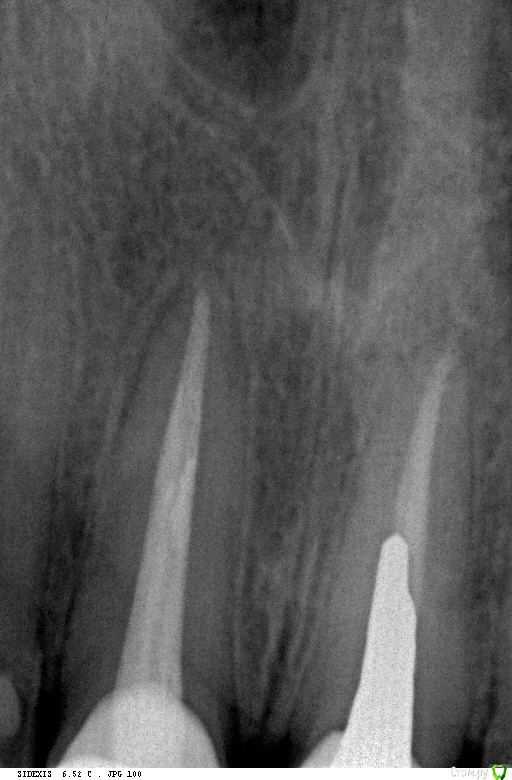

Доброй ночи, такая ситуация, 3 года назад поставили коронку единичка, 9 июля начала болеть десна там где эта коронка, сказали воспалился сосочек десны, полоскал и мазал специальной пастой 20 июля перестало болеть, 4 сентября опять начало болеть причем намного сильнее, пошел к стоматологу он сказал не страшно прописал нимисин и пасту, боль стала невыносимой и заметил, что коронка опустилось чу чуть, пошел к другому стоматологу сделали снимок и стучал по зубам больно очень было 2-ке, сказал пульпит на ней и удалил пульпу, про коронку сказал, что не поменять коронка так и будет, но проблема в том, что жевать не могу нажимаю на коронку и десне больно и она ходит чу чуть, можно ли ее снять и заного одеть?

Снимки фото прилагаю.